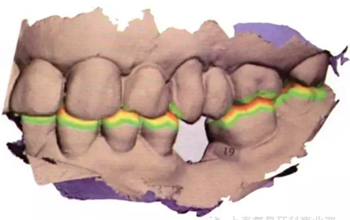

將從CBCT中獲得的數(shù)字掃描文件和DICOM文件導(dǎo)入到Implant Studio軟件中(3Shape),一種新的空間技術(shù)可以創(chuàng)建口腔內(nèi)真實情況的三維重疊圖像和放射圖片。Implant Studio中的修復(fù)性設(shè)計工具可用來在修復(fù)表面圖片上創(chuàng)建一個處于理想修復(fù)位置的符合功能性和美觀性的虛擬牙冠(圖4a-d)。

圖4a:初始數(shù)字化牙冠設(shè)計的側(cè)面冠

圖4b:虛擬牙冠設(shè)計在最大牙尖交錯位時上下頜骨的側(cè)面觀

圖4c:最后牙冠設(shè)計的合面觀

圖4d:最后牙冠設(shè)計的側(cè)面觀